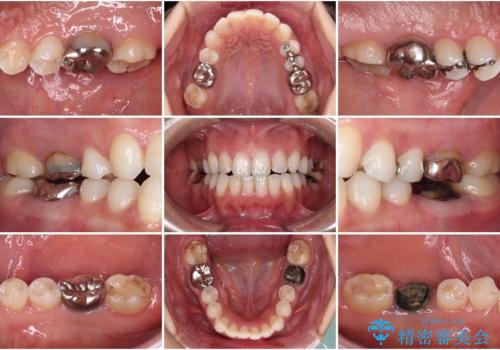

[ セラミック・インプラント全顎治療 ] 長年悩まされている歯の治療にケリをつけたい

![[ セラミック・インプラント全顎治療 ] 長年悩まされている歯の治療にケリをつけたいの症例 治療前](https://seimitsushinbi.jp/wp/wp-content/uploads/2022/01/699ba08b6e311b07f9d2ea9a5b757aea-500x350.jpg?v=1642042101)